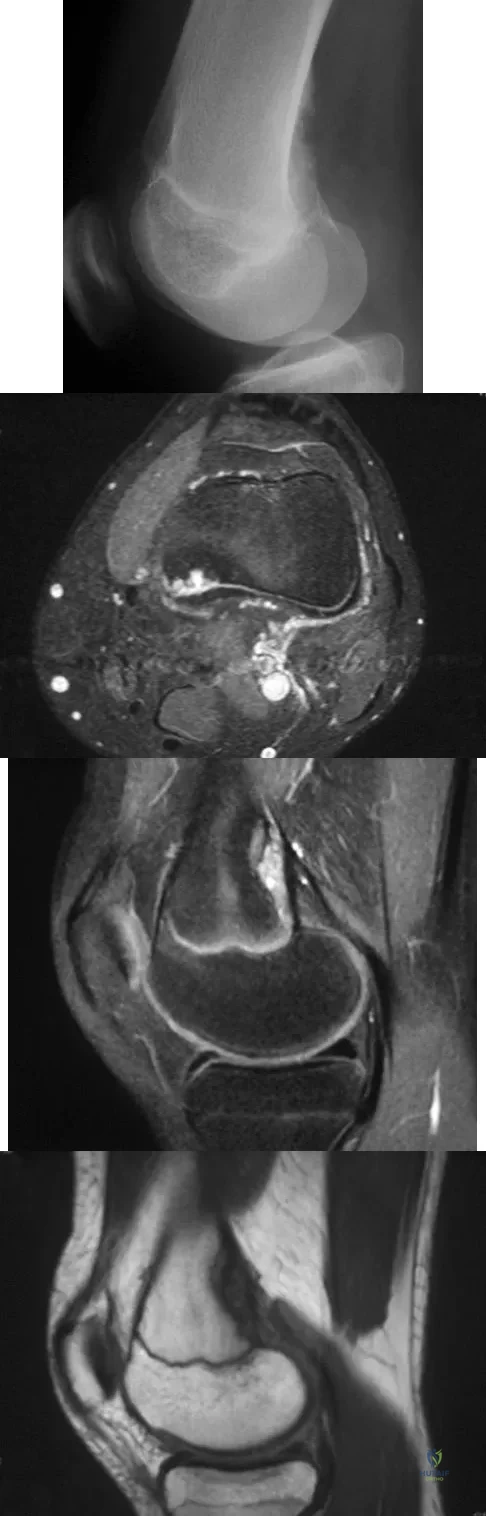

Question 41

A 14-year-old girl reports bilateral patellofemoral symptoms. Based on the radiograph and MRI scans shown in Figures 23a through 23d, what is the next most appropriate step in management of the lesion?

Explanation